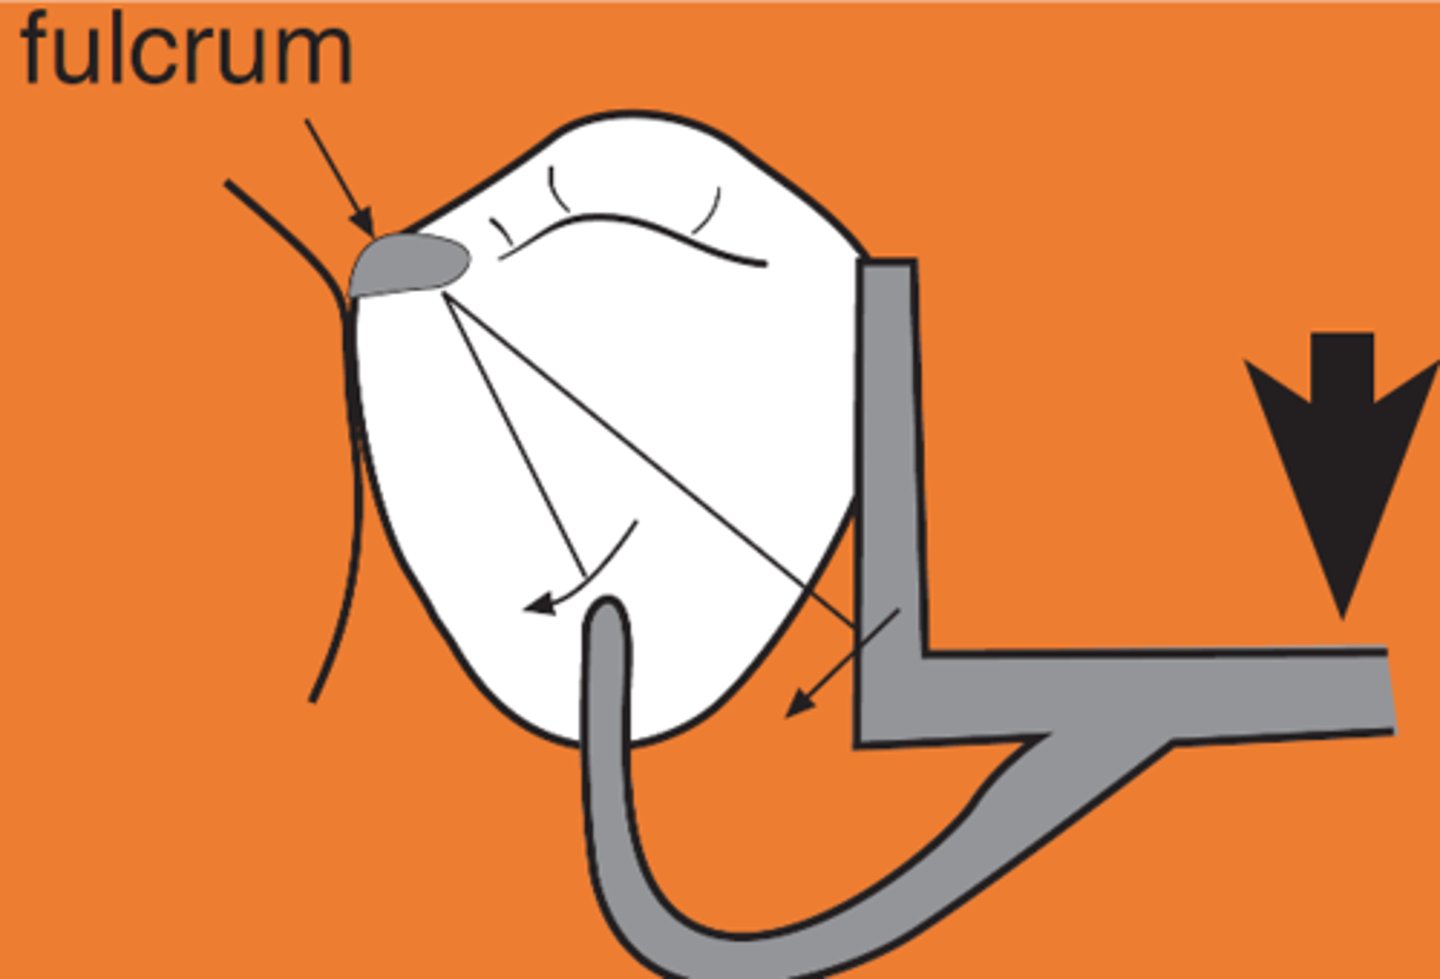

Indirect retainer

associated with extension base RPDs,

rotation occurs around rests: fulcrum line is through the most distal rest on each side, assist the direct retainers in preventing displacement through lever action on the opposite side of the fulcrum line when the denture base moves away from the tissues in rotation around the fulcrum line, prevents rotational displacement of denture from supporting soft tissues

90°

An indirect retainer Ideally should be _______ from primary fulcrum line midway between the most distal rests, as far from fulcrum line as possible